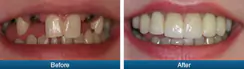

Broken Teeth

Full Mouth Rehabilitation

Esthetics